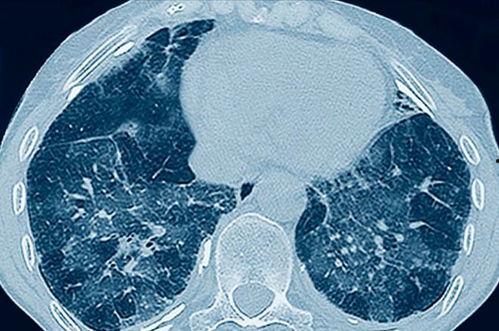

首先,让我们来欣赏一下肺呼吸视频的精彩片段。视频中,你可以看到肺部随着呼吸的起伏,就像一个巨大的气球,时而膨胀,时而收缩。这个过程就像一场奇妙的魔术表演,让人不禁感叹大自然的神奇。

1. 呼吸过程:肺呼吸视频详细展示了呼吸的全过程,包括吸气、呼气、肺泡扩张和收缩等。这些过程看似简单,实则复杂,每一个环节都至关重要。

2. 肺功能:肺呼吸视频让我们直观地看到了肺部的功能。原来,我们的肺部不仅负责呼吸,还能过滤空气中的杂质,保护我们的身体健康。